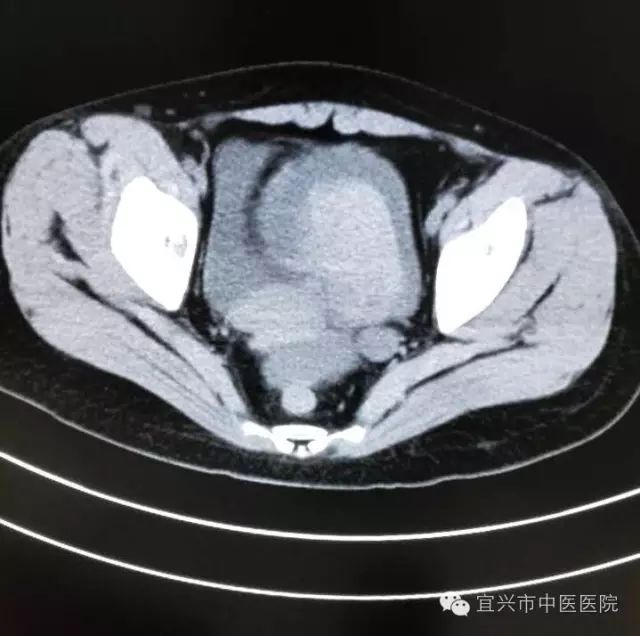

进一步查CT显示:膀胱积血、腹盆腔积血,保留导尿也引出了暗红色液体。

(资料图片)